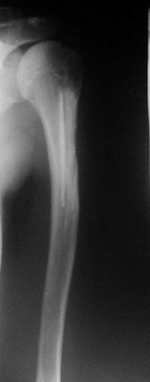

С момента внедрения в клиническую практику ДКИ разной степени деминерализации, выполненных по технологии ЦИТО, прошло более 12 лет. За это время значительному ко-личеству больных были произведены реконструктивные операции с помощью костно-пластического материала «Перфоост» [13]. Результаты лечения и сроки органотипического восстановления значительных объемов костной ткани в области аллопластики позволили утверждать, что разработанные в тканевом банке ЦИТО ДКИ безопасны и обладают высокими остеоиндуктивными свойствами [5]. Адекватное количество пластического материала, его разные формы и прочностные характеристики способствовали полному заполнению пострезекционных дефектов (рис. 1, 2).

| Рисунок 2. Больная К. 15 лет. Аневризмальная киста левой бедренной кости. Пластика дефекта губчатыми аллоимплантатами: | ||

| а) рентгенологическая картина состояния до операции; | б) состояние после операции; | в) через 3 месяца после операции; |